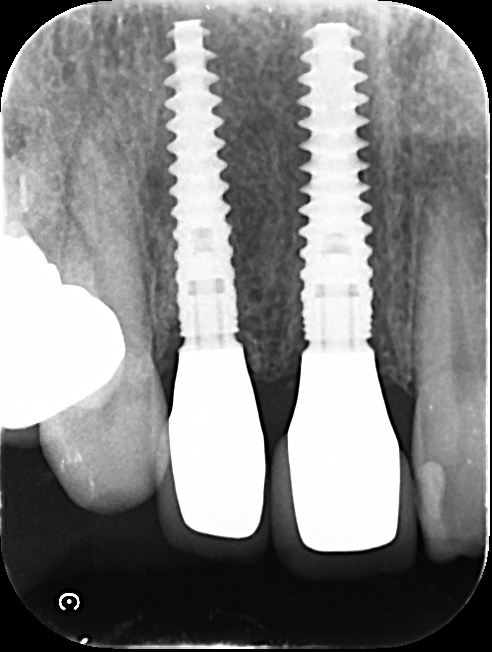

右上2番目の歯も白い器具のところまで破損していましたので残す事ができず、抜歯いたしました。

前歯に2本インプラント治療を行い、同時に前歯部に歯肉移植(インプラントの周りに歯茎を移植することで審美的に治療をする事ができます)をいたしました。

しっかり歯茎の状態が落ち着くまでしばらく様子を見ていただきます・・・

とても自然で綺麗な被せ物をセットできました✨

治療前と比べると歯茎の状態も引き締まりとても健康的なきれいな仕上がりです。